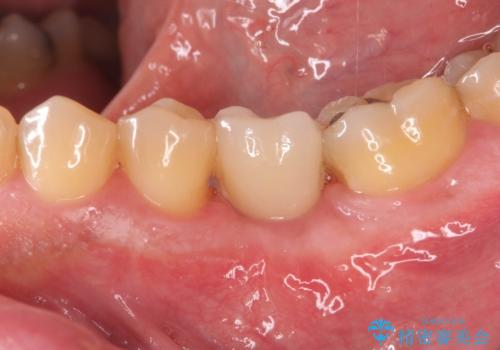

インレー下に再発した虫歯 セラミッククラウンによるやり替え